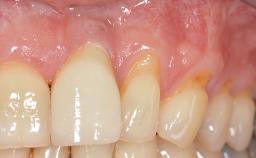

Variations in soft-tissue volume, evidenced either by an overabundance (Evian and coworkers 1993; Levine and McGuire1997; Dolt and Robbins 1997) or by a deficiency of soft or hard tissue can complicate implant-supported rehabilitations in the esthetic zone (Lorenzana 2008; Lorenzana and coworkers 2009). The present case illustrates the replacement of a failing upper left lateral incisor complicated by generalized severe gingival recession in the esthetic zone.